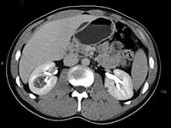

- 单项选择题男,45岁, 右腰部隐痛不适伴无痛性肉眼血尿1月,结合所示图像, 最可能的诊断是 ( )

A、右肾癌

B、右肾血管平滑肌脂肪瘤

C、右肾感染性囊肿

D、右肾盂癌

E、右肾脓肿